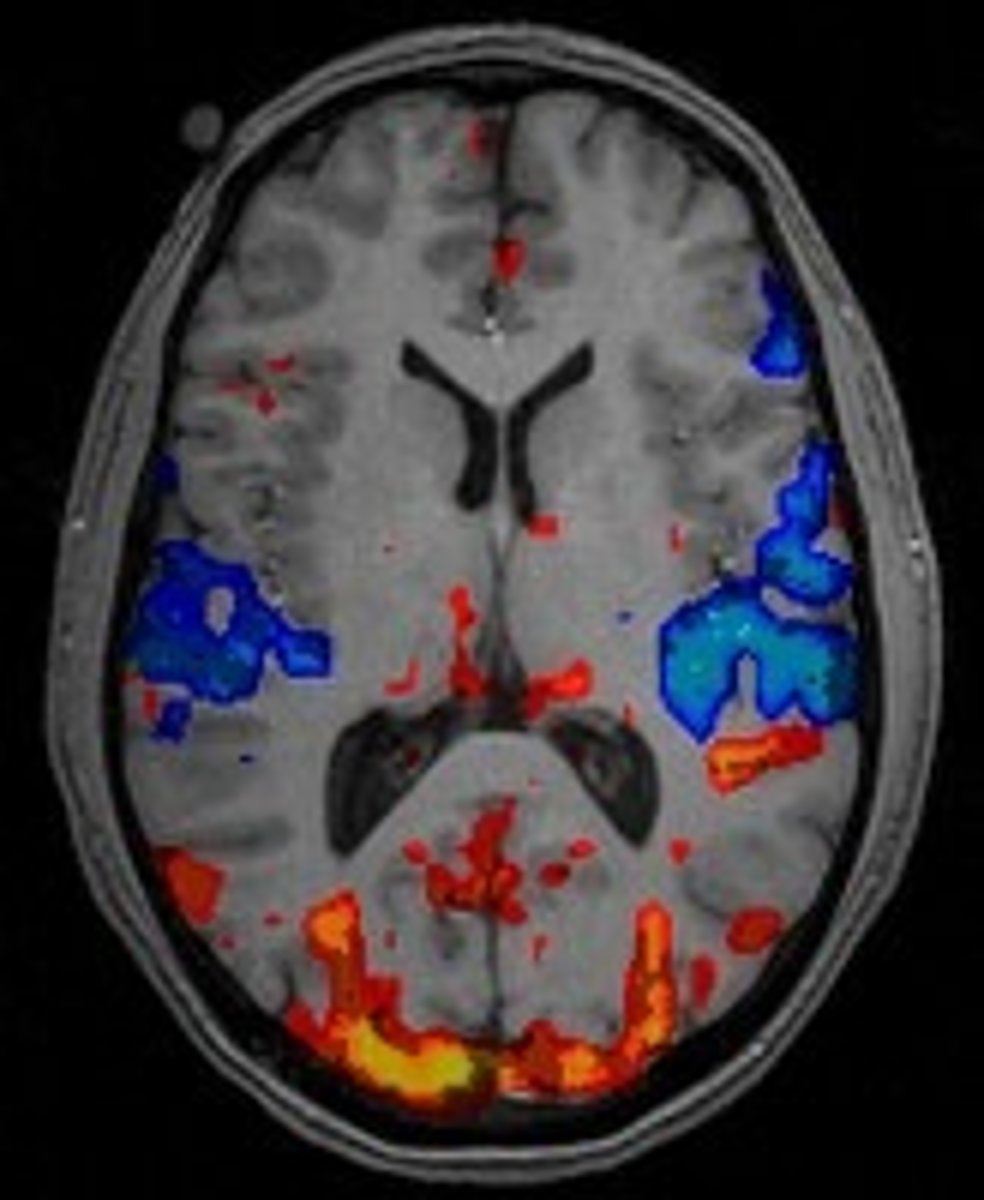

fMRI

Magnetic imaging of the brain which shows active areas of the brain. Ex: Seeing the visual cortex light up on a monitor while a patient looks at photographs.